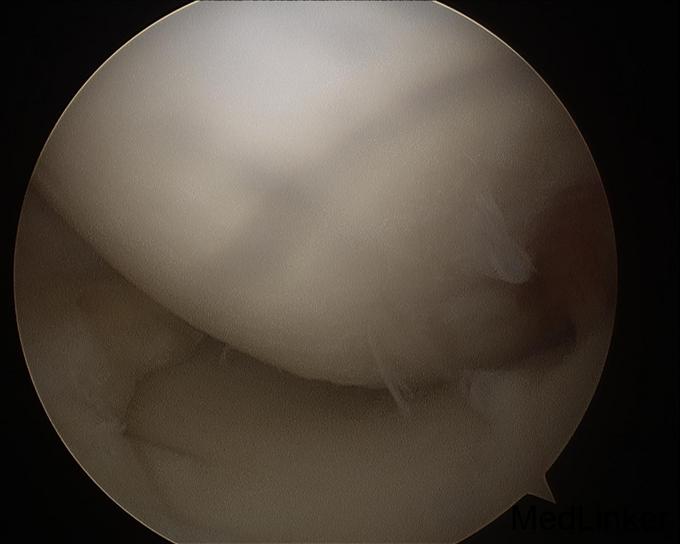

诊断:左膝前交叉韧带重建术后,左膝半月板损伤。 治疗:左膝内固定取出术+左膝关节镜下探查+左膝前交叉韧带皱缩+内侧半月板成形术

随访:患者术后扶拐行走2周。2周后活动度恢复正常,亦恢复正常行走。 讨论:该患者为前交叉韧带自体肌腱重建术后9年,难得有机会进行second look。术中发现重建韧带形态完整,但纤维松散,术前查体亦有松弛现象。术中予以紧缩处理后,术后松弛度明显改善。